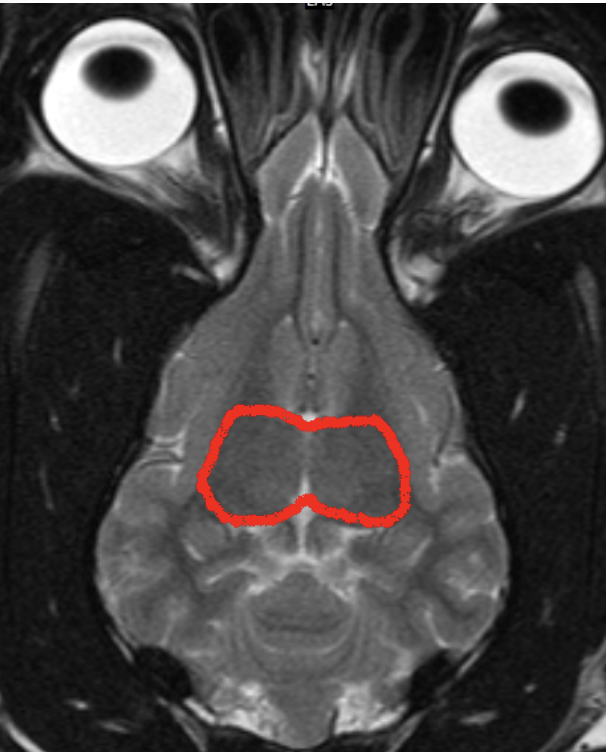

what structure is shown here

telencephalon

2 cerebral hemispheres